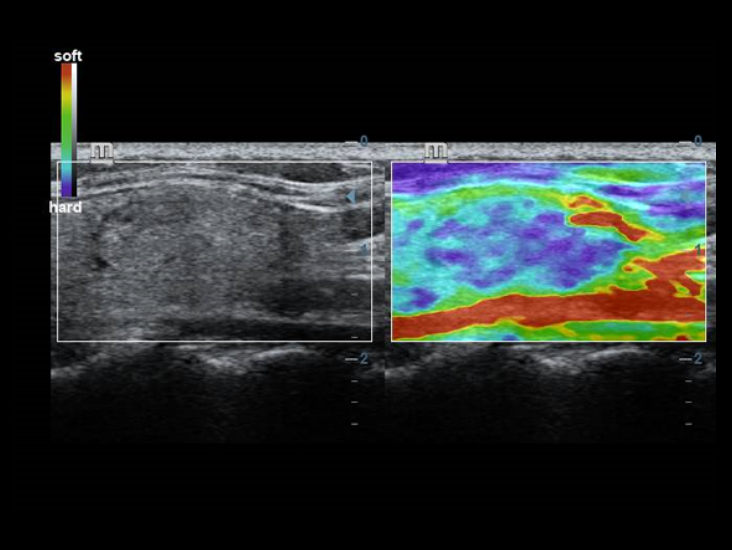

Tecnologie di imaging classiche: migliorare la qualitĂ a scopo diagnostico

Con l'applicazione delle tecnologie di imaging tradizionali, migrate da sistemi a ultrasuoni consolidati, DC-40 con Full HD offre immagini di qualitĂ estremamente dettagliate.

- iClear (tecnologia di imaging con riduzione del rumore)

- PSH(Phase Shift Harmonic Imaging)

- iBeam: ?tecnologia di imaging spaziale âCompoundâ